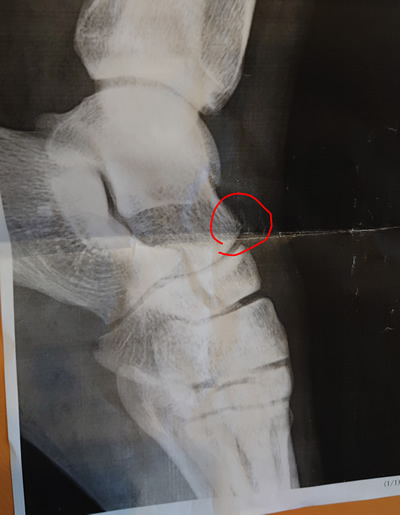

左距骨頭部骨折 大阪市旭区 大学生 陸上部 男性

ハードルで強打し距骨頭部骨折

小さな骨折で転移はあまりありません

エレサスにて、治療

3w程でほぼ疼痛は0に!